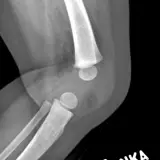

Des cas entièrement interactifs avec les outils attendus d'un PACS — défilement, fenêtrage, zoom, déplacement, mesures, ROI et mode plein écran.

Des annotations détaillées mettent en évidence les résultats clés directement sur les cas. Cliquez sur les résultats liés dans les descriptions de cas pour accéder à leur emplacement exact sur l'examen.

Défilez, déplacez, fenêtrez et zoomez comme sur une station PACS de travail